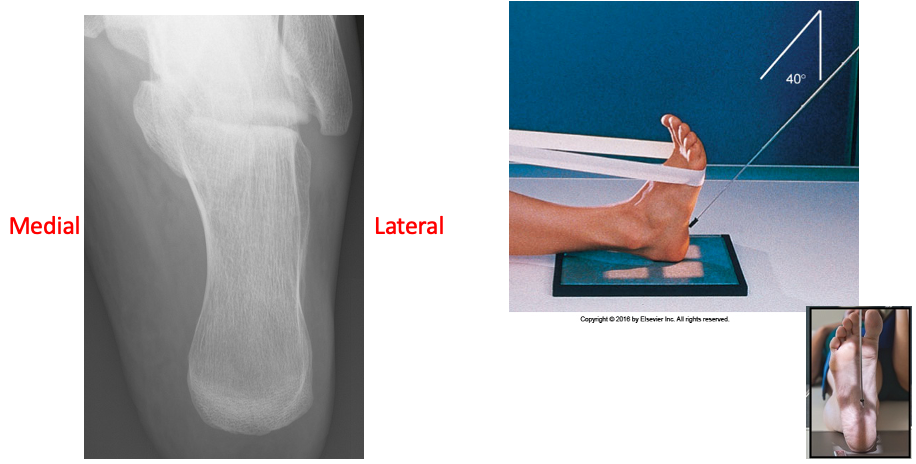

Plantodorsal Axial Calcaneus

• IR 8x10 Portrait, 40 SID

• Pt seated or supine with leg fully extended. Center and align ankle joint to CR and portion of IR being exposed. Dorsiflex foot so plantar surface is near perpendicular to IR.

• CR angle 40º cephalic to long axis of foot entering base of third MT exiting at level distal to lateral malleolus. Collimate close to region of calcaneus